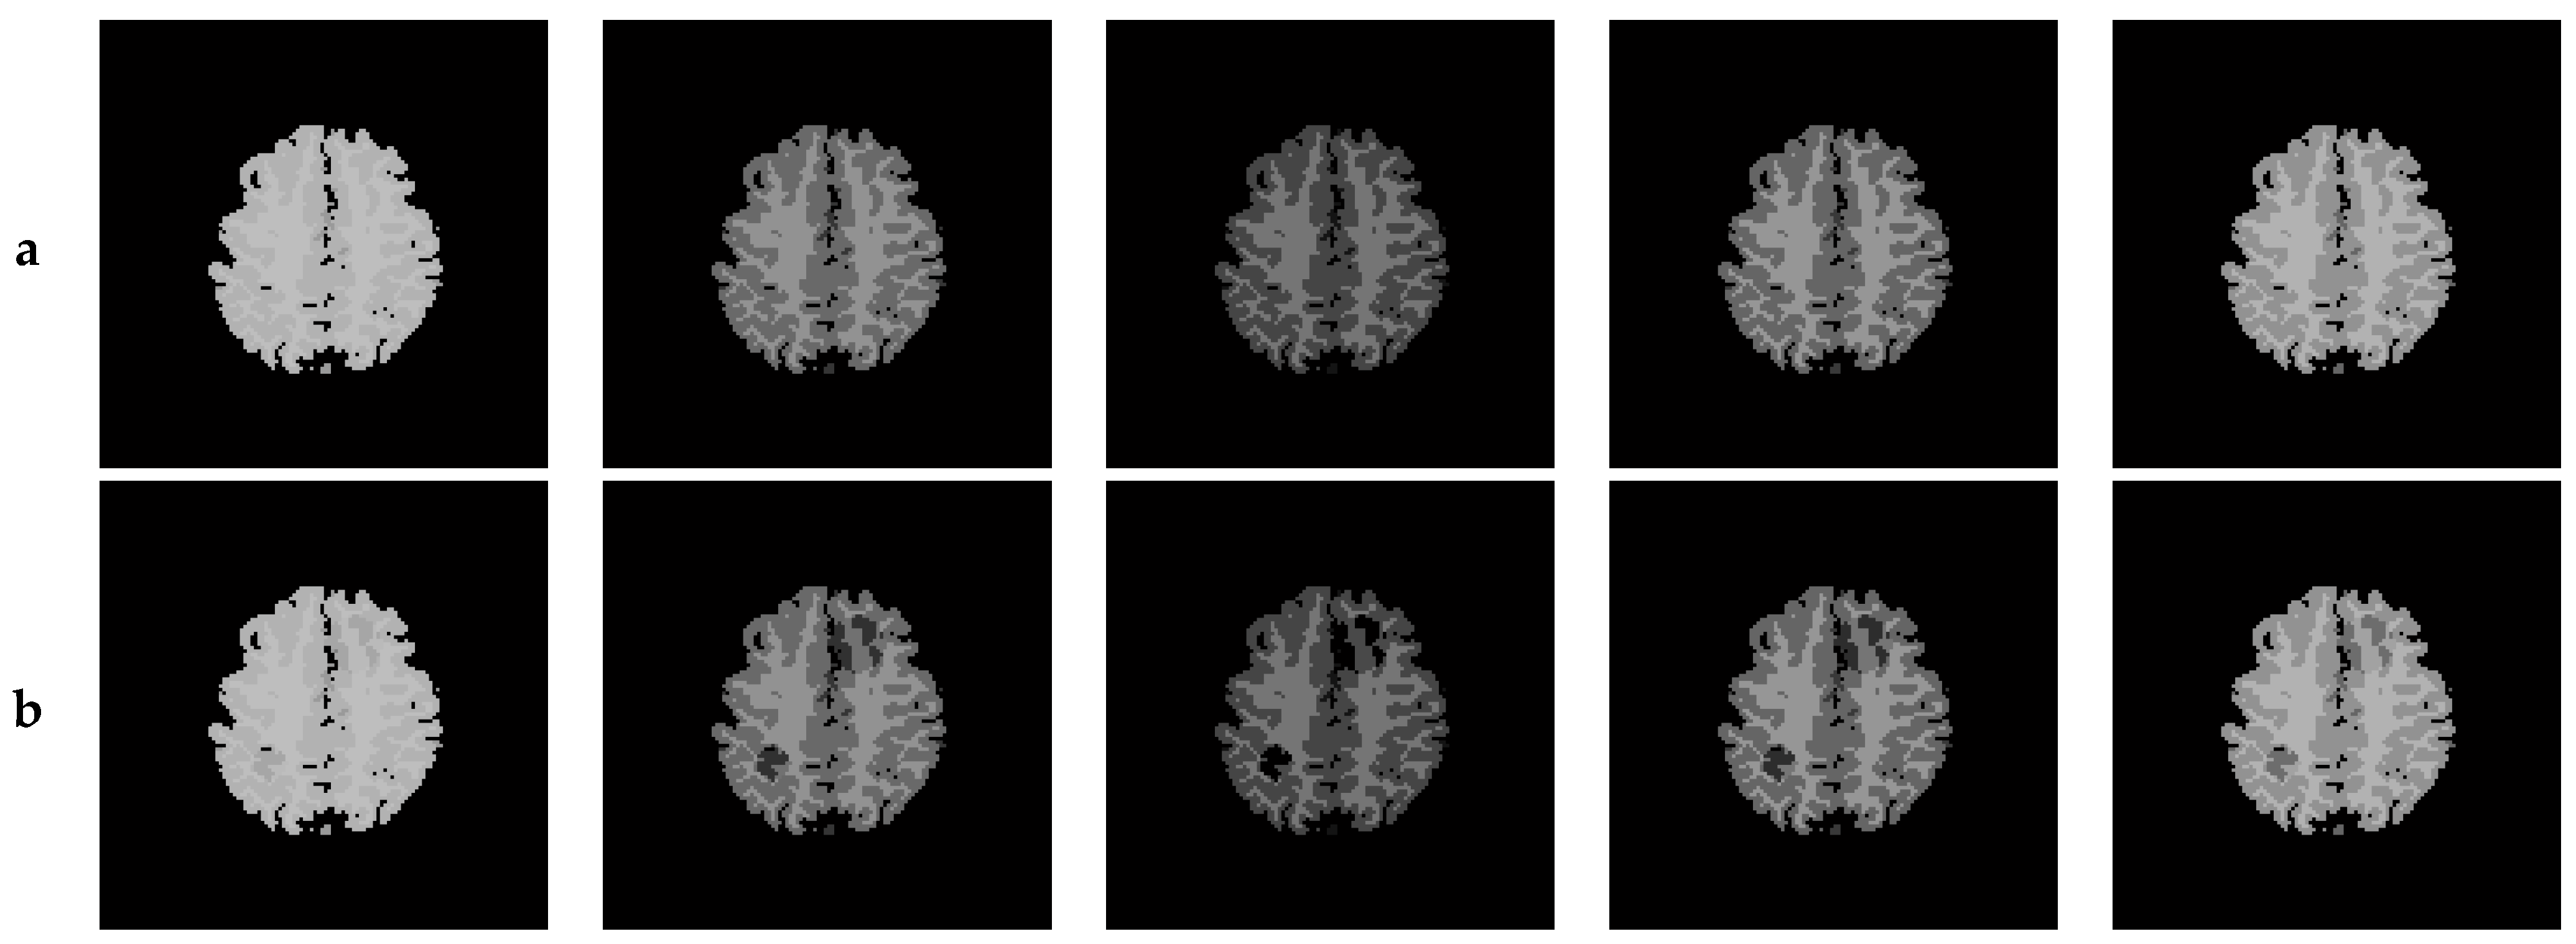

7. Results—Exemplary DSC-MRI Study Models